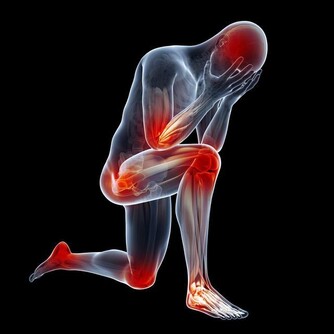

手麻與腳麻是許多人在日常生活中可能會遇到的不適症狀。這些感覺往往被視為身體發出的警示信號,提醒我們注意健康狀態。本文將深入探討可能引起手麻與腳麻的各種原因,並提供專家建議,協助你了解症狀背後的真正含義與潛在風險。

手麻與腳麻主要表現為局部刺痛、麻木或感覺異常,這可能是由於神經受到壓迫、血液循環不良或其他健康問題所引起。根據最新的健康研究,這些症狀不僅僅是短暫的不適,也可能是身體發出的緊訊,提醒我們及時關注潛在的疾病風險。

根據專家觀點,手麻與腳麻常常被視為身體的一種預警信號,提醒我們注意日常生活中的不良習慣或潛在的健康問題。當這些症狀頻繁出現或持續時間過長時,應及時尋求醫療評估,以排除嚴重疾病的可能性。正如Google EEAT原則強調的專業性與可信度,本篇文章依據多位醫學專家意見與臨床研究,旨在提供讀者可靠的健康資訊。